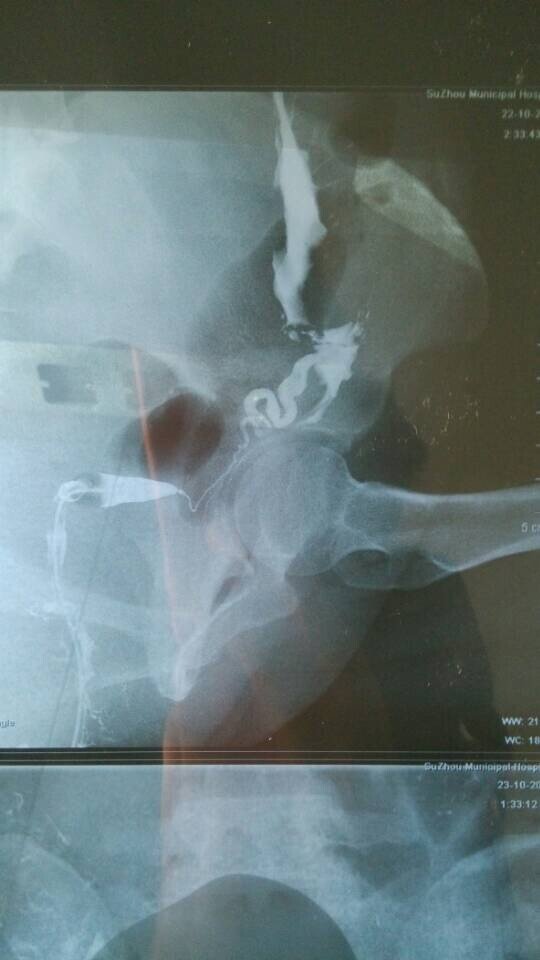

输卵管造影显示一侧不通,做宫腹腔镜成功率多大? 结婚一年未孕,14年10月份做了输卵管造影,显示右侧不通,所以医生建议做宫腹腔镜,但是我在网上查到说这个手术不是所有的都能疏通,而且要全身麻醉,副作用较大,还会感染炎症,我本身有霉菌性阴道炎,且在11年有做过一次人流,想请哪位专家帮我看看我这个情况做这个手术右侧疏通的几率多大、这个手术真的成功率很低吗?我该怎么办?而且连续两个月堵的那一侧在排卵,我可不可以打促排卵的药促使两边都排卵?还有输卵管上举做人工是不是会宫外孕啊??问题很多,多谢各位专家了 点击展开 匿名用户 2015-01-04 15:14 推荐回答 你好,做腹豆柴腔镜手术比较好一点,让自己自然怀孕比较好,做人工受精成功率也不是很高的而涌渐神且畸形率比较唉究大。 cn#BfuaaGVkLG 2015-01-05 14:58 宝宝知道提示您:回答为网友贡献,仅供参考。 相关问题 输卵管近端堵塞;用宫腹腔镜手术成功率多少?求专家指点都快离婚了因为不孕 输卵管造影多久可以做宫腹腔镜 输卵管不通做了宫腹腔镜手术已经快一年了,还未孕,还用再做造影检查吗

结婚一年未孕,14年10月份做了输卵管造影,显示右侧不通,所以医生建议做宫腹腔镜,但是我在网上查到说这个手术不是所有的都能疏通,而且要全身麻醉,副作用较大,还会感染炎症,我本身有霉菌性阴道炎,且在11年有做过一次人流,想请哪位专家帮我看看我这个情况做这个手术右侧疏通的几率多大、这个手术真的成功率很低吗?我该怎么办?而且连续两个月堵的那一侧在排卵,我可不可以打促排卵的药促使两边都排卵?还有输卵管上举做人工是不是会宫外孕啊??问题很多,多谢各位专家了